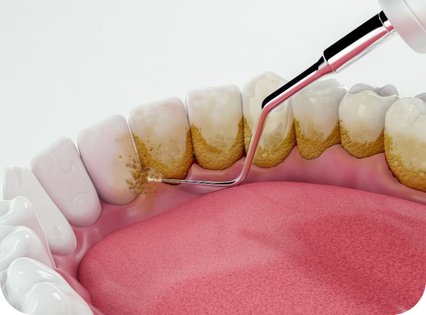

Karang gigi dibersihkan menyeluruh, termasuk area sulit dijangkau, sehingga gigi dan gusi tetap sehat lebih lama.

Nikmati pengalaman scaling tanpa rasa sakit dengan teknologi dental spa. Pembersihan lebih lembut, nyaman dan menyeluruh.